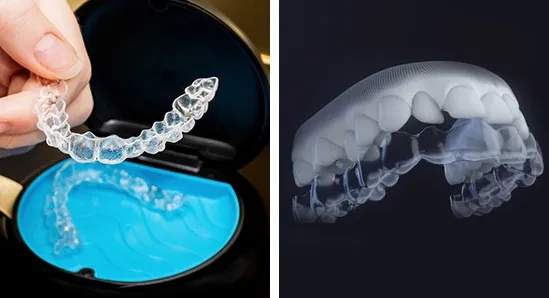

Tổng quan về Zenyum và Invisalign Trong những năm gần đây, nhu cầu chỉnh nha ngày càng tăng cao, không chỉ bởi lợi ích về sức khỏe

Invisalign là gì? Lịch sử phát triển của Invisalign bắt nguồn từ năm 1997, khi hai nha sĩ, Tiến sĩ Zia Chishti và Brian Quan, nhận ra